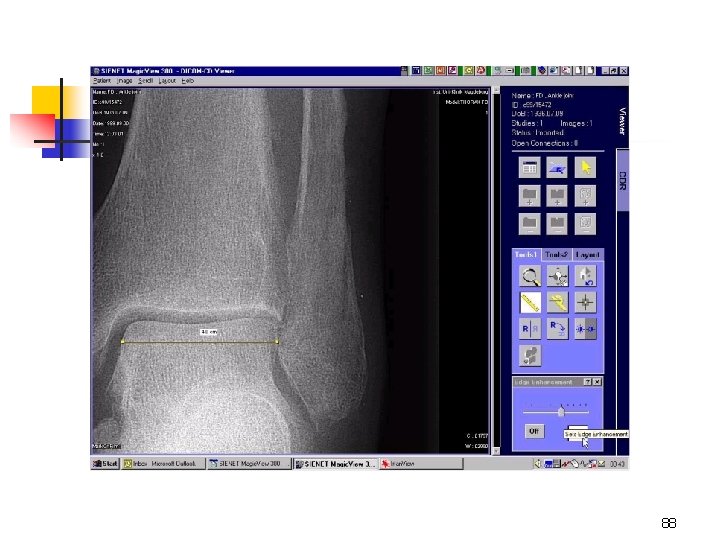

QC – Reader (replaces Darkroom & Processor & Chemicals Diagnostic Viewer (replaces film, storage & viewboxes) 87

88